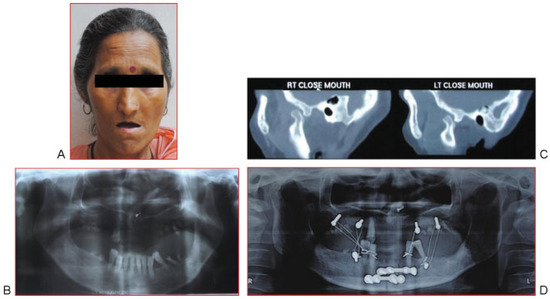

Case Report 2